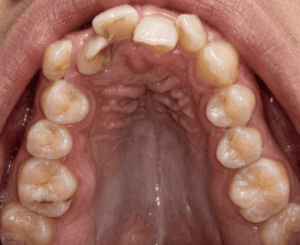

① 口の天井が高くて狭い(上顎が狭い)

上顎の幅が狭いと、口の天井がドーム状に高くなります。すると鼻の奥の空間も狭くなり、鼻で呼吸しにくくなることがあります。自然と口を開けて呼吸するようになり、それがいびきにつながることもあります。

2004年の研究で、いびき・無呼吸のある方47名とそうでない方47名の口の形を比べたところ、いびき・無呼吸のある方はのどの入り口あたりの空間が有意に狭いことがわかっています。(Johal & Conaghan, Angle Orthod. 2004)